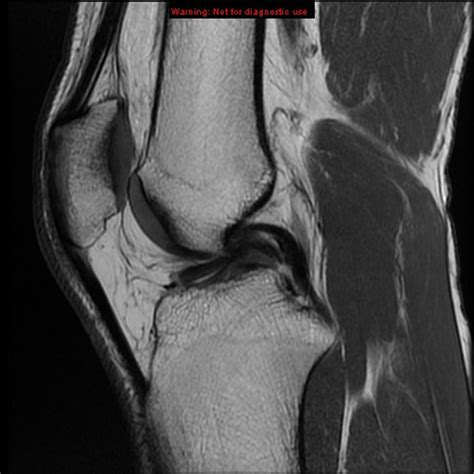

A Bucket Handle Meniscus Tear is a specific type of meniscus tear where a longitudinal tear occurs, causing a portion of the meniscus to displace and flip into the joint space. This displacement can resemble the handle of a bucket, hence the name. This type of tear is often more severe than other types of meniscus tears and can lead to significant knee instability and pain.

• Imaging Tests: Magnetic Resonance Imaging (MRI) is the gold standard for diagnosing meniscus tears. It provides detailed images of the knee joint, allowing for accurate identification of the tear.